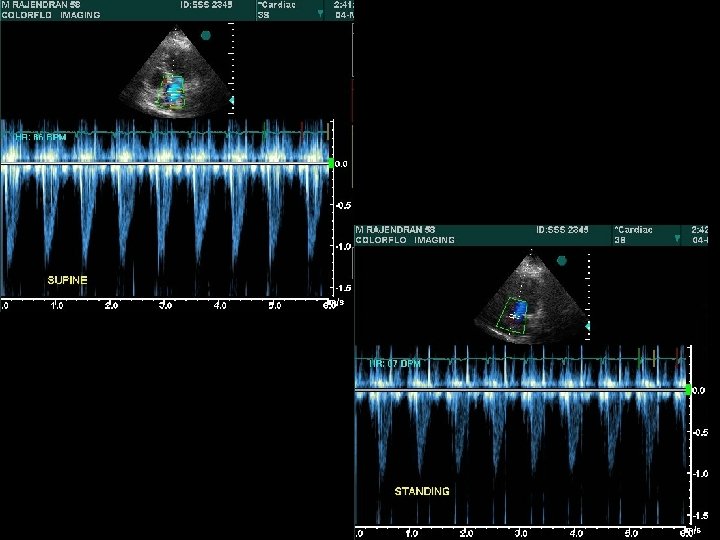

Abrupt standing • S 2 split which may be wide, may narrow down , while the fixed split may persist • A 2 OS interval widens – differentiates from wide split of S 2 • All murmurs ( except MVP/HOCM) decrease • ESM of HOCM becomes louder and longer • Click occurs earlier, murmur becomes longer in MVP – loudness shows variable response

Squatting • Increased venous return and CO > augments most murmurs atleast initially (AS, PS, MR, AR, VSD) Right heart murmurs do so earlier • Increased ventricular volume > murmur of HOCM ↓ murmur of MVP ↓→ • Ejection murmur of TOF ↑

Hemodynamics of Squatting T Murakami AHJ 2002; 15: 986– 988

T Murakami AHJ 2002; 15: 986– 988